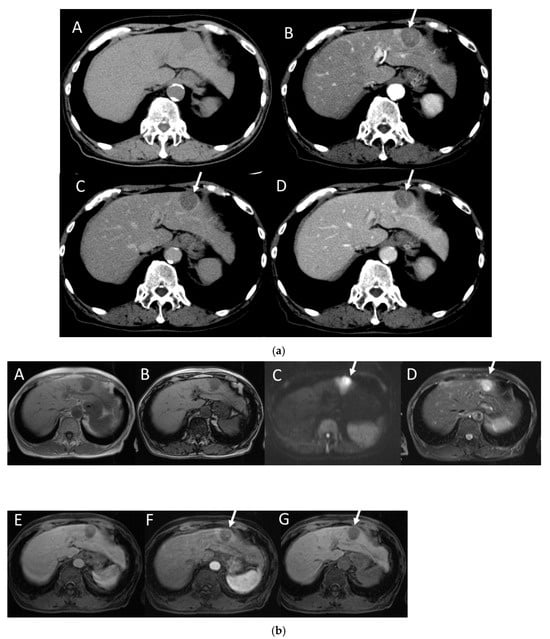

4.6. Fibrolamellar Hepatocellular Carcinoma (FL-HCC)

4.7. Combined Hepatocellular and Cholangiocarcinoma (cHCC-CCA)

4.8. Steatohepatitic HCC (SH-HCC)